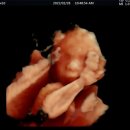

집 귀염둥이 커리가 벌써 11살이 되었어요. 🐶 노령견 접어들면서 건강 관리가 제일 걱정이었는데, 이번에 알게 된 버디닥 어플 덕분에 노원에 있는 노원온동물병원에서 기분 좋게 강아지건강검진 마치고 왔습니다! 주말에 다녀온 따끈따끈한 후기 남겨볼게요. ✨ Previous image Next image 📱 버디닥 앱으로 세상...

[노원온동물병원 후기] 안녕하세요 오늘은 고양이 건강검진 후기를 가져왔어요! ISFM Gold 인증 고양이 친화병원에서 레오 건강검진 받았어요 🐈 우리 레오는 예민한 아이예요. 낯선 환경에 가면 바로 긴장해서 하악질도 하고, 검사할 때마다 걱정이 많았는데요. 다행히 집근처에 고양이 친화 병원이 생겨서 방문했답니다...